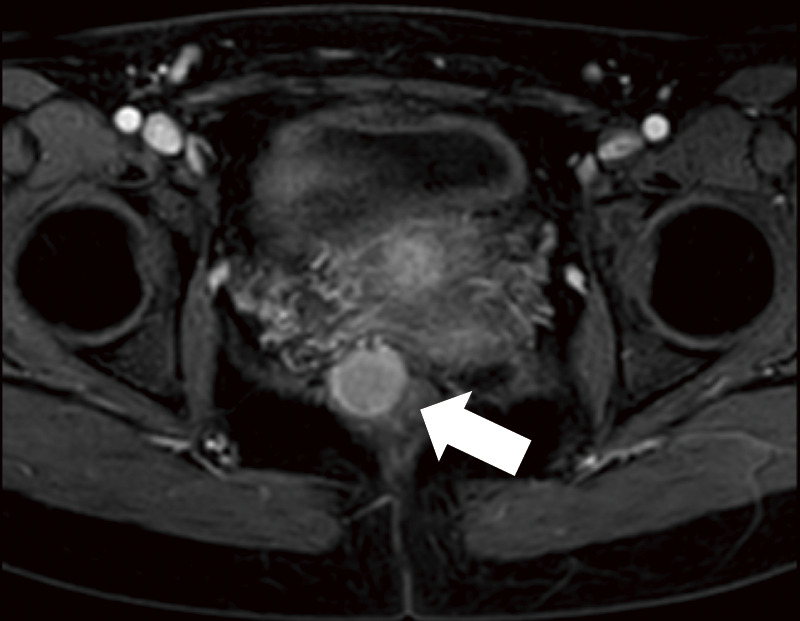

Case presentation: A 29-year-old woman experienced a severe perineal tear during the first vaginal delivery, which led to the incidental discovery of a 20-mm rectal NET. Four months after the perineal tear, the gynecology and digestive surgery teams ensured that the tear wound had completely healed and anal function was preserved. The patient underwent robot-assisted ultra-low anterior resection with lymph node dissection. The procedure was successfully completed, preserving anal function, and histopathology confirmed an NET (G2, pT2N2aM0, pStage IIIB). The patient recovered smoothly and was discharged on the seventh postoperative day.